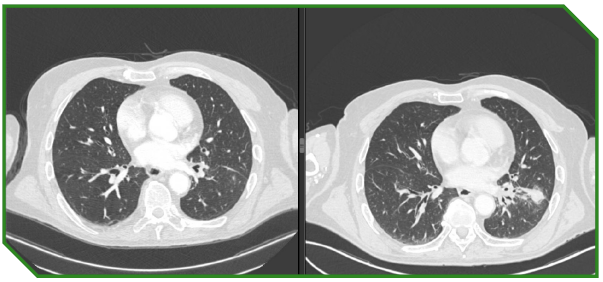

Paciente masculino de 78 anos com carcinoma espinocelular de laringe, tratado inicialmente com abordagem definitiva local, evoluindo posteriormente com recidiva local e progressão metastática pulmonar. Ao longo do curso da doença, foi submetido a múltiplas linhas terapêuticas, incluindo cirurgia, radioquimioterapia, quimioterapia sistêmica e imunoterapia isolada e em combinação, refletindo a complexidade do manejo longitudinal do R/M HNSCC.